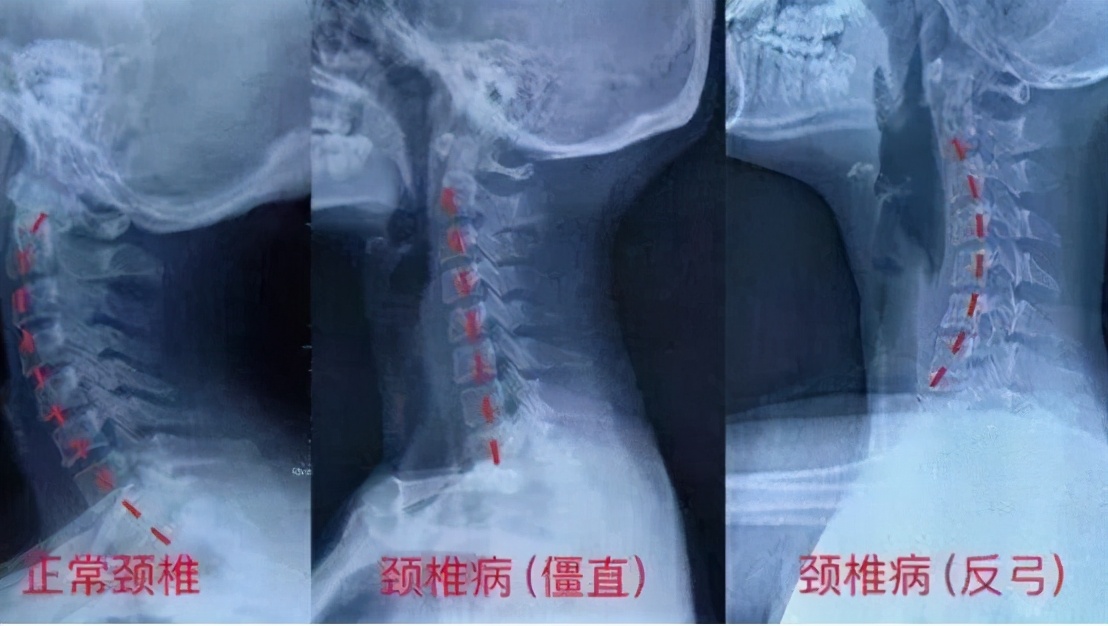

长期不良习惯会改变颈椎正常生理曲度

我们从医学上解释颈椎病的发生机理,由于颈椎长期承受超负荷压力,造成患儿正处于发育期的颈椎正常生理曲度发生病理改变,出现生理曲度变直,改变了颈部原有的生物力学平衡,从而导致颈部局部组织炎症水肿,表现出临床症状。影响生长期颈椎的发育,导致严重后果。